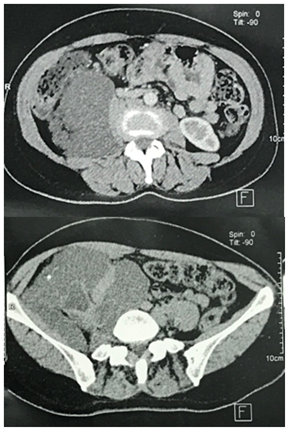

We present here the case of a 50-year-old woman who consulted for a mild right low back pain with palpable abdominal mass since several months. The clinical examination revealed a painless tumefaction of the right iliac fossa (Figure 1). A CT-scan performed showed a large right retroperitoneal cystic polylobed mass, well limited, measuring 15 cm x 10 cm x 9 cm, pushing forward the digestive loops and pushing up the right kidney, containing calcifications, without enhancement after contrast injection, and without evidence of adjacent structures infiltration, evoking a retroperitoneal cystic lymphangioma (Figure 2) and (Figure 3). The patient underwent an exploratory laparotomy, which showed a large whitish retroperitoneal cyst, extending from the right iliac fossa to the right hypochondrium (Figure 4). Given the appendix was not individualized, we suspected then, during surgery, an appendiceal mucocele. During dissection, we assisted to a tumoral rupture, and approximately 500 milliliters of a thick, gelatinous mucoid substance was sucked. The peritoneal cavity was already protected by surgical drape. We went an en-bloc and complete resection of the tumor (Figure 5). The post-operative course were normal. The histological study concluded to a mucinous cystadenoma (Figure 6). After a one-year follow-up, control CT-scans showed no signs of recurrence.

In 11 to 47 %, the appendiceal mucocele is completely asymptomatic.7 It is more frequent when the aetiology is not neoplastic.12 Biology is rarely useful. Indeed, the elevation of tumor markers (CEA and CA 19-9) was reported only once by Igor Mishin.15 The key of diagnosis is imaging, and the most adequate imaging modality is computed tomography, preferably interpreted by an experienced radiologist. Indeed, it is difficult to establish the anatomic relations between the mass and other organs, and the appendicular origin, especially when the mass is large and retroperitoneal.16 In most cases, it would be a cystic, poly-lobed, paracaecal mass, with or without parietal calcification.16 The presence of calcifications helps making difference between appendiceal mucocele and acute appendicitis.16 Typical ultrasonography’s aspect is a right iliac fossa oval hypoechoic mass, with posterior acoustic enhancement.9,17 Magnetic resonance imaging (MRI) can help define the mucocele’s limit and differentiate the mass (whose content is gelatinous) from ascites. Indeed, in T2-weighted sequences, it reveals a different and less intense signal than the ascites.18,19 However, calcifications are less visible on MR.18,19 Colonoscopy is usefull when a colonic tumor is suspected, or to verify the integrity of the mucosa.3 Metabolic imaging (18F-fluorodeoxyglucose positron emission tomography) has been studied for patients with metastatic appendiceal tumors, but the results showed a low sensitivity, and, thereby, is not indicated.18,20